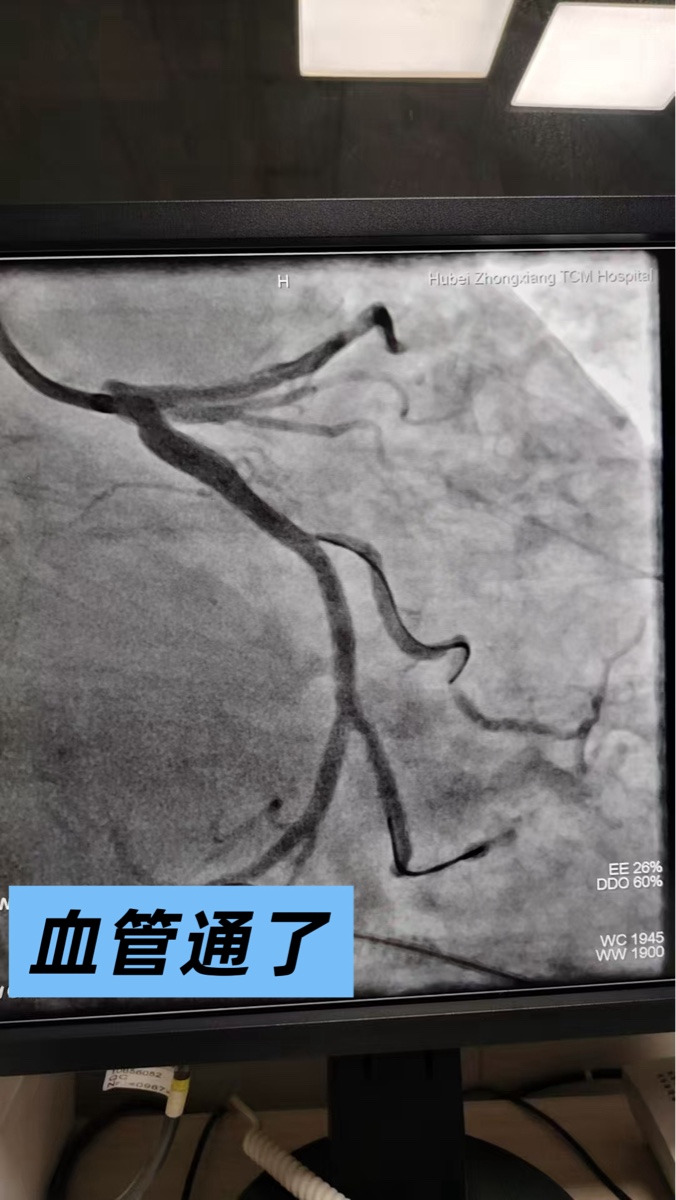

2026年2月1日,是我此生刻骨铭心的日子。突如其来的心肌梗死,如同一道晴天霹雳,将我瞬间推向死亡的边缘,在意识模糊、剧痛缠身的时刻,我被紧急送入中医院心病科,从此开启了与死神赛跑、惊心动魄的十天。

是中医院心病科徐国炳主任、陈炙炜医师组成的医疗团队,用精湛的医术与赤诚的仁心,为我铺就了一条重生之路。徐国炳主任临危不乱,带领团队争分夺秒展开抢救,以过硬的专业能力与果断的救治方案,硬生生将我从死亡谷里拉了回来,让我从濒死的边缘重获生机,给了我第二次生命。